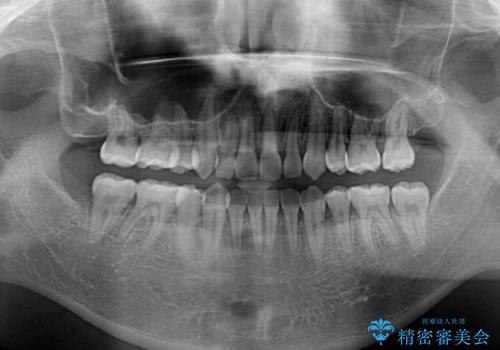

上顎の左右側切歯(前から2番目)が裏側に隠れいてる状態で、咬み合わせや清掃性に大きな問題が認められました。

叢生が著しいため、上下左右の小臼歯4本を抜去し、目立たないワイヤー装置にて矯正治療を行うこととしました。

下顎の歯列全体が右側にずれているため、右下のみ第二小臼歯を抜歯し、上顎は補助装置を使用して、極力上下の正中を合う位置にて咬み合わせを改善するようにしました。